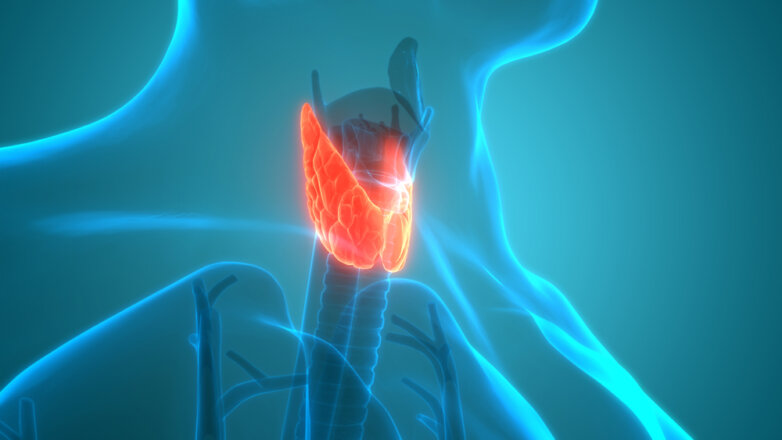

Ποιες είναι οι μοναδικές πτυχές της σεξουαλικής υγείας για τα διεμφυλικά και μη δυαδικά άτομα;

Σωματικά ζητήματα υγείας - Ψυχοκοινωνικοί παράγοντες - Πρόσβαση στην υγειονομική περίθαλψη